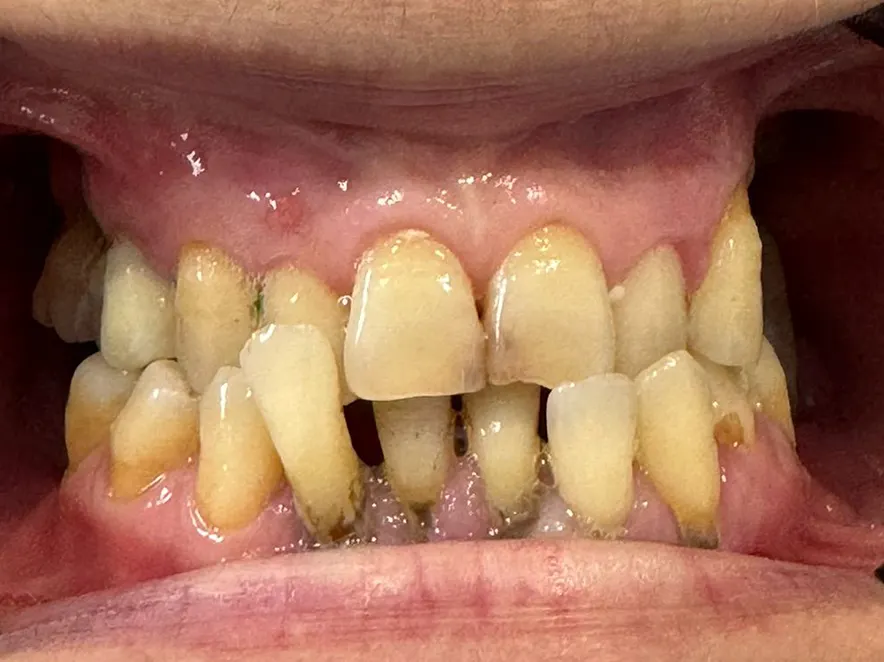

At MC Dental Glen Waverley, Dr Joe recently completed a patient’s smile transformation. He carefully worked through a tailored treatment plan that restored health, improved function, and gave the patient back their smile, plus their confidence! (Photos shown below)

Many patients come to us with multiple dental concerns that require a stepped approach to treatment. A single patient’s journey may involve a combination of fillings, root canal therapy, periodontal (gum) treatment, veneers, crowns or bridges, and sometimes even implants. Every case is different, and that’s why our team takes the time to plan each stage carefully, working with you to prioritise comfort, function, and results.